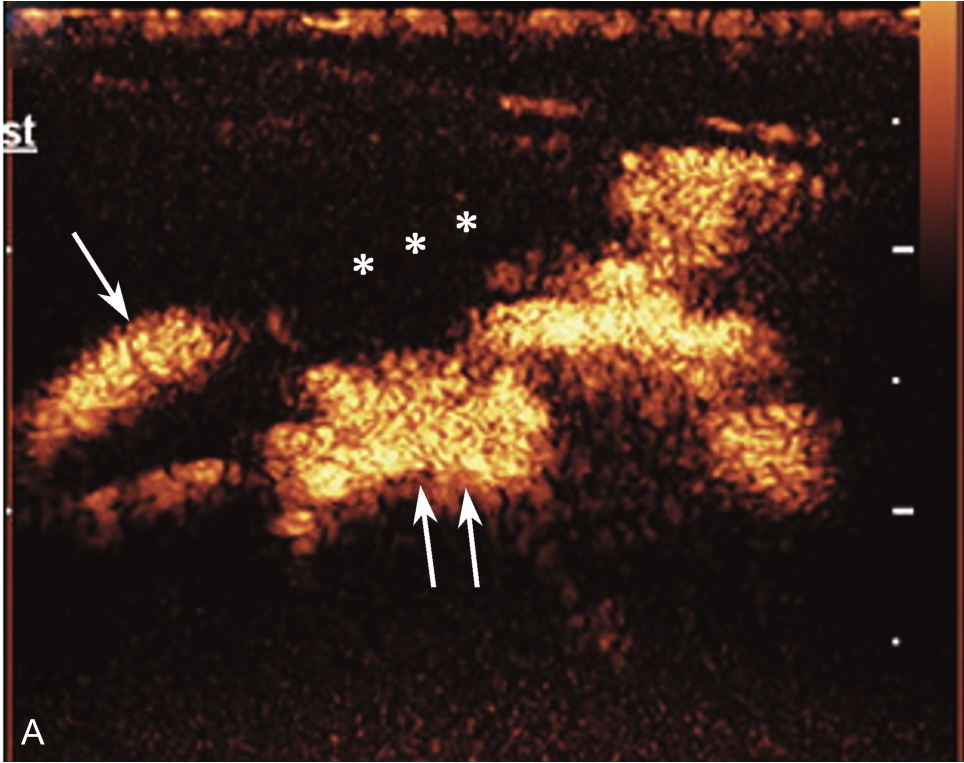

▲ 图2-1-9 超声引导下肩峰下-三角肌下滑囊造影图(二)

A.超声引导下滑囊内注入超声造影剂后,滑囊呈线状高增强,肌腱内可见局限性高增强,提示肌腱滑囊面部分撕裂(箭头);B.二维超声显示冈上肌腱(SUP)回声不均匀(箭头),但未见明显撕裂,HH:肱骨头